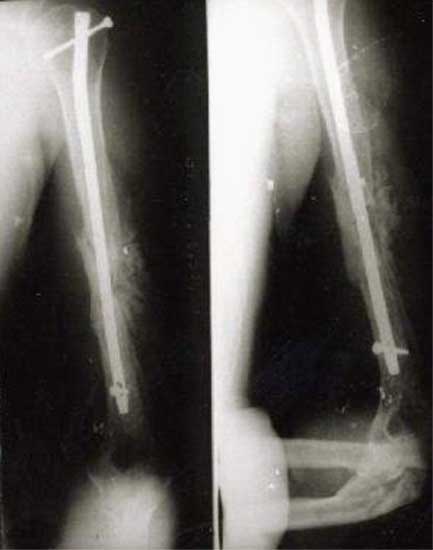

股骨远段骨折,4次钢板固定均失败,改用带锁髓内钉固定,7个月后骨折愈合。